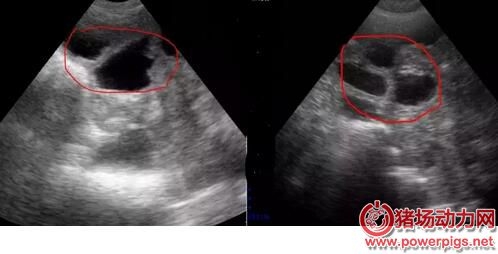

配完種之后要做的事情是什么? 肯定是檢查母豬是否妊娠啦..... 那么問題來了,到底什么時(shí)候檢查妊娠最為合適? 按理來說,早檢查可以盡快把沒有懷孕的母豬查找出來,而晚檢查可以盡可能把早期胚胎死亡的母豬也查找出來。 其實(shí)最好的策略是從輸精后第18天開始就用公豬來檢查母豬是否返情。隨后從第21天開始,第三周、第四周連續(xù)做兩次妊娠掃描診斷。 應(yīng)該也有不少吃瓜群眾挺好奇不同階段的懷孕情況是怎樣的? 不同階段B超結(jié)果 第18-21天 在豬受孕18天后,B超已經(jīng)可以檢測到胚泡,但是由于此時(shí)的胚泡形態(tài)較小,檢測時(shí)不容易被發(fā)現(xiàn),需要操作員消耗大量時(shí)間來尋找。 母豬早期孕檢技巧: 1.母豬配種后18-21天; 2.測定時(shí)先找到膀胱暗區(qū),小角度緩慢變換探頭探掃方向,在膀胱暗區(qū)前上方“亮帶”以上細(xì)致查找疑似的黑洞。 第21-35天 22-25天的胚胎很容易發(fā)現(xiàn),此時(shí)將探頭放在檢測“三角區(qū)中”,只要位置正確立刻能發(fā)現(xiàn)孕囊,此時(shí)孕囊主要顯示為一個(gè)個(gè)的“黑洞”。 測孕小技巧 1.18-25天期間胎囊極速增長 2.早期胎囊為圓形或橢圓形,1-2天之后多數(shù)變?yōu)椴灰?guī)則 第25-35天 25-35天,孕囊會(huì)放慢變大的速度,逐步從“黑洞”內(nèi)可看到一些白色的亮光出現(xiàn),是胎兒的超聲反射,又稱為胎體反射。 測孕小技巧 1.25天以后可見胎體反射,此后胎體占了胎囊的大部分 2.32天時(shí),能顯示胎兒骨骼鈣化的強(qiáng)回聲 第35-65天 35-65天,孕囊和胎兒會(huì)一起長大,會(huì)更容易發(fā)現(xiàn)“黑洞”中有亮斑,系胎兒的超聲反射,也稱胎體反射,此時(shí)的圖形孕囊和胎體反射會(huì)比25-35天期間更大,更明顯?!昂诙础泵娣e減少,是因?yàn)檠蛩疁p少。 測孕小技巧 1.35天時(shí),呈現(xiàn)胎兒骨骼鈣化的強(qiáng)烈回聲,羊水面積減少 2.45天時(shí),胎兒體腔分化 第65-100天 65-110天,胎兒已經(jīng)長大,羊水減少。80天,胎兒的肋骨可清晰見到,從不同角度可呈現(xiàn)“虛線橢圓”亮斑,或者“弧形”亮斑。 測孕小技巧 1.80天時(shí),胎兒脊柱清晰顯示 2.95天時(shí),胎兒脊椎、胸骨及體腔分辨清晰 不過也有些小伙伴反映,母豬經(jīng)常返情,到底是什么原因呢?妊娠成功又需要些什么條件呢? 發(fā)情周期約21天。在授精后18-24天發(fā)情的母豬(沒有懷孕)稱為規(guī)律性返情母豬。以此類推,在42天或者63天左右返情的母豬也稱為規(guī)律性返情母豬,返情高峰期分布在這些天。分散在其他天數(shù)的稱為非規(guī)律性返情母豬。 返情 返情/復(fù)配的原因 最常見的原因——授精管理差;催情不足;發(fā)情不充分/太短;授精時(shí)間選擇好;3周后返情;發(fā)情檢查不足;授精時(shí)間選擇不好;“發(fā)情周期”小于18天;3周和/或6周后返情 配種員:態(tài)度,工作壓力 管理系統(tǒng):催情/發(fā)情檢查、輸精管理、數(shù)據(jù)記錄 營養(yǎng):喂料量和飼養(yǎng)管理 欄舍:飼養(yǎng)密度、環(huán)境、光照、溫度、占用率 母豬:出生缺陷,發(fā)育狀況 繁殖與傳染病 種豬場,疾病很少成為繁殖問題的一個(gè)重要因素,傳染病通過以下兩套途徑殺死胚胎: 傳染病病毒損壞了胚胎、胎膜或者子宮,引起胚胎死于子宮中(如細(xì)小病毒、藍(lán)耳病毒); 發(fā)燒引起前列腺素的大量釋放,前列腺素會(huì)引起流產(chǎn)(如豬丹毒、流感、腸道病毒、經(jīng)典豬瘟、肺或腸道傳染病引起的發(fā)燒)。因此在發(fā)燒期間要用退燒藥。如果多個(gè)母豬幾乎同時(shí)流產(chǎn)的話,要考慮傳染病可能是問題的源頭。 寄生蟲:由疥螨、豬虱或者皮膚狀況不好引起的皮炎會(huì)使母豬焦躁不安。這種焦躁不安也是造成母豬返情的一個(gè)原因。 如果懷疑是疾病問題(不吃料、精神萎靡、皮膚發(fā)白、糞便),一定要測量母豬的體溫。涂點(diǎn)潤滑劑或者唾液,將溫度計(jì)插入母豬肛門內(nèi)至少5cm。讓溫度計(jì)的頂端緊貼著腸壁,糞便或者腸道內(nèi)的空氣都會(huì)影響測定結(jié)果。健康妊娠母豬的體溫是38-39°C,超過39.5°C就是發(fā)燒了。 氣溫 熱應(yīng)激會(huì)導(dǎo)致母豬流產(chǎn)、返情。 夏天,不要在一天中最熱的時(shí)候喂豬;在豬舍向陽面,用塑料薄膜、石灰或者乳化漆遮蔽窗戶;提供平和、安靜的環(huán)境;高溫時(shí)不搞預(yù)防接種;每天檢查配種舍、待配舍和妊娠舍的溫度。 9月中旬到10月底,會(huì)出現(xiàn)秋季繁殖力下降現(xiàn)象:后備母豬發(fā)情開始變慢,非規(guī)律性返情和規(guī)律性返情或流產(chǎn)越來越多。 秋天晝夜溫差最大,為預(yù)防秋季繁殖力下降,從7月底開始將光照時(shí)間增加到每天16個(gè)小時(shí),同時(shí)要確保配種舍和待配舍晚上的溫度不要太低(<18°C),提前做好通風(fēng)管理,避免出現(xiàn)賊風(fēng)。提高斷奶后的和配種后的母豬的飼喂量。因?yàn)榈蜏貤l件下,更多的能量用于維持需要,從而使得用于繁殖的能量減少。 分析 少于18天的發(fā)情期從生理學(xué)角度上講是不可能的。 3周左右的規(guī)律性返情的責(zé)任在于配種員,此外妊娠早期會(huì)有胚胎死亡。對于36-48天或者56-68天出現(xiàn)的返情,3周時(shí)出現(xiàn)的返情被錯(cuò)過的可能性極大。 25-36天非規(guī)律性返情的原因常常是胚胎死亡。在此期間未被發(fā)現(xiàn)的母豬過21天會(huì)再返情,即在49-56天返情。 妊娠成功的因素有哪些 配種員:催情、發(fā)情檢查、輸精時(shí)間、輸精技術(shù) 公豬:精液質(zhì)量、精液儲(chǔ)存、精液貨架壽命、公豬差 母豬/胚胎:母豬體況不好、應(yīng)激、疾病、光照(強(qiáng)度和時(shí)間) 再者,又有大伙們表示母豬流產(chǎn)也不少見,求解求解? 胚胎死亡發(fā)生的階段 排卵:卵子少或質(zhì)量低(營養(yǎng)不良); 受精:授精不佳,原因:配種員或公豬; 胚胎死亡:胚胎可能死于各種原因,如疼痛或瘸、轉(zhuǎn)運(yùn)應(yīng)激、喂料站工作不正常、疥螨、為爭奪統(tǒng)治地位而打斗、環(huán)境不良、能量負(fù)平衡; 胎兒死亡(妊娠35天以后):子宮內(nèi)空間不足(胎兒太多)或者死于發(fā)燒/疾?。ú怀R姡?。 胚胎存活的關(guān)鍵 在妊娠35天之前保持平和、安靜是必不可少的,因?yàn)榇饲芭咛ψ訉m內(nèi)環(huán)境變化還非常敏感。從妊娠后第12天到第18天,胚胎發(fā)出雌激素信號,所以黃體完整保留,妊娠繼續(xù)。骨骼的形成于妊娠后第30天。 來源:溫氏養(yǎng)豬公開課 |